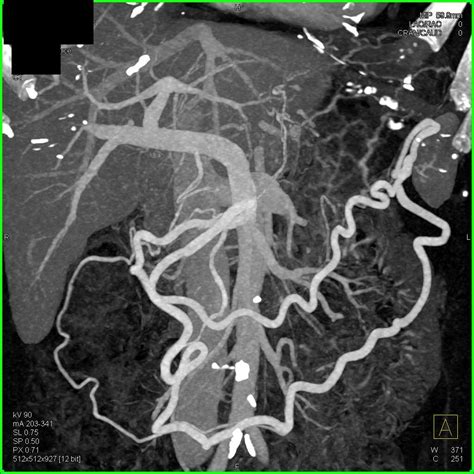

Pancreatic adenocarcinoma is a particularly aggressive form of pancreatic cancer that originates in the exocrine cells of the pancreas. Early detection and accurate diagnosis are crucial for effective treatment. One of the most important diagnostic tools for pancreatic adenocarcinoma is the Pancreatic Adenocarcinoma CT Scan. This imaging technique provides detailed images of the pancreas and surrounding tissues, helping healthcare professionals to identify tumors, assess their size and location, and plan appropriate treatment strategies.

A Pancreatic Adenocarcinoma CT Scan is a non-invasive imaging procedure that uses X-rays to create detailed cross-sectional images of the body. These scans are particularly useful for diagnosing pancreatic adenocarcinoma because they can:

• Detect tumors in the pancreas.

• Determine the size and location of the tumor.

• Assess the extent of the cancer's spread to nearby organs and lymph nodes.

• Guide biopsy procedures to obtain tissue samples for further analysis.

• Monitor the effectiveness of treatment over time.